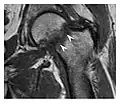

The greater tuberosity of the humerus is also an illustrative location of occult fractures. The osseous injury may follow seizures, glenohumeral dislocation, forced abduction, or direct impaction. They are commonly discovered on MRI in symptomatic patients with suspicion of rotator cuff tear. Coronal images are best suited for detection. They appear as crescentic oblique lines surrounded by a bone marrow edema pattern (Figure 5). The rotator cuff must be inspected since associated ligamentous lesions are common. In the ankle, malleoli and tarsal bones should be checked carefully for any cortical disruptions and radiolucent lines that may reveal a fracture. Awareness of the exact location of the pain will help direct the attention of the interpreter when searching for very subtle signs of fracture (Figure 6).[1]

Figure 5: Traumatic fracture of the greater tuberosity in a 51-year-old man presenting with left shoulder pain after a fall on ice. Initial radiographs were normal. Coronal inversion recovery MRI shows a fracture line (arrow) through the greater tuberosity surrounded by a bone marrow edema pattern.[1]